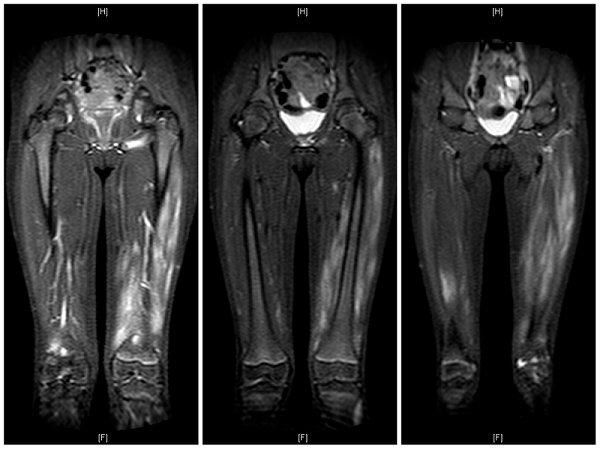

Ante la sospecha de una miopatía inflamatoria, se solicita un electroneurograma y electromiograma (ENG/EMG) de miembros inferiores, ecocardiograma transtorácico, electrocardiograma (ECG) y capilaroscopia, que resultan normales. Se realiza una RM de control que revela datos de edema muscular en la región proximal de ambos miembros inferiores, especialmente en el cuádriceps izquierdo (Fig. 1). La biopsia incisional del músculo cuádriceps femoral derecho demuestra ausencia de actividad inflamatoria, pero con un discreto aumento de lípidos con atrofia leve de fibras tipo 2, sobrexpresión focal de MHC-1 coincidente con una sobrexpresión leve de atrofina y un mínimo componente linfocitario T endomisial, sugiriendo un componente de miopatía inflamatoria en resolución.

Figura 1. RM de miembros inferiores que revela datos de edema muscular en la región proximal de ambos miembros inferiores, especialmente en el cuádriceps izquierdo

Dentro de las pruebas complementarias, las más usadas son el ENG/EMG, que suele mostrar un patrón miopático con denervación, la RM, y la biopsia muscular2,5,7. La RM muscular es una prueba no invasiva que puede mostrar áreas de inflamación muscular y permite estudiar áreas musculares más amplias2,5. Es útil como control del curso de la enfermedad2,5,8 y puede utilizarse para seleccionar las zonas afectadas donde realizar la biopsia muscular2,5. La biopsia muscular es la prueba definitiva para establecer el diagnóstico, permitiendo valorar la presencia de infiltrado inflamatorio linfohistiocitario, atrofia de predominio perifascicular y necrosis de las fibras musculares1, así como estudiar la sobreexpresión del HLA tipo I en el sarcolema y sarcoplasma de la célula muscular4,5,6. Existen discrepancias sobre la realización de biopsia a todos los pacientes. Algunos expertos recomiendan realizarla a todos los pacientes con DMJ para mejorar la clasificación, el tratamiento y pronóstico a largo plazo4.